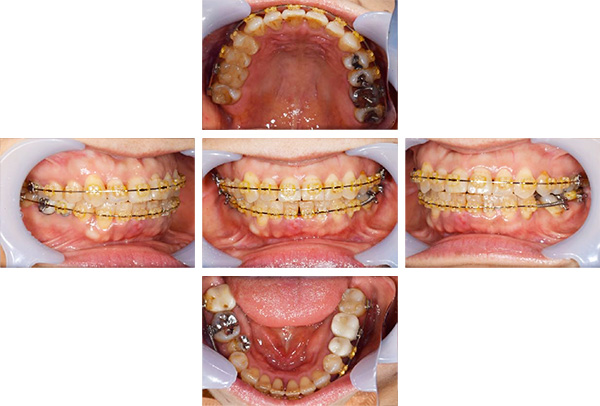

治療中

担当医師所見

矯正装置をつけています。だんだん八重歯が動いてきているのがわかります。今回のケースでは、抜歯を行わずに矯正ができました。